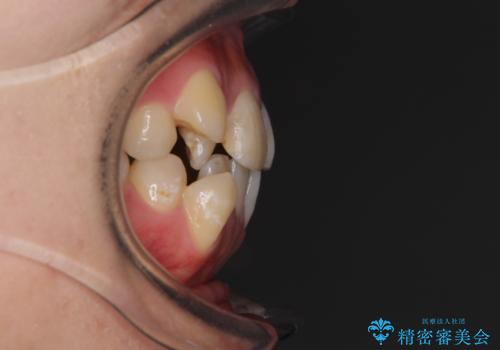

右側のみ上下小臼歯を抜歯したため、上下の正中が右にずれてしまう可能性があります。

また、元々右側は上下が咬み合っていないため、矯正をしても咬み合わないことも考えられました。